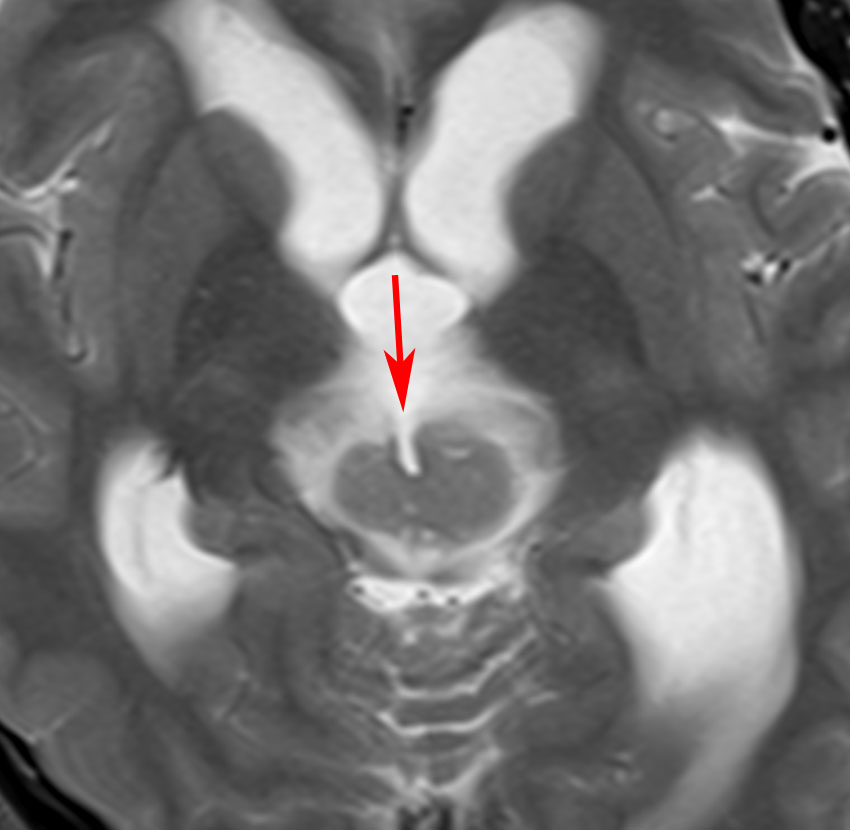

この例は18歳,HCG 0.1mIU/ml,尿崩症で発症しました。神経下垂体ジャーミノーマなので,下垂体前葉のみが残って後葉から視床下部が腫瘍化しています。よくよく見ると松果体にもごく小さな腫瘍があります。右のCISS画像で松果体の腫瘍化が明瞭です。

経鼻生検術で下垂体後葉部分がgerminomaということを確認してからICE (IFO/CDDP/VP-16)を1コース加えて3週間後の画像です。腫瘍は灰白隆起の部分を残してほぼ消失しています。松果体部の腫瘍も消えています。典型的なgerminomaの化学療法反応性を示しています。下垂体前葉機能は正常,尿崩症も少し良くなりました。